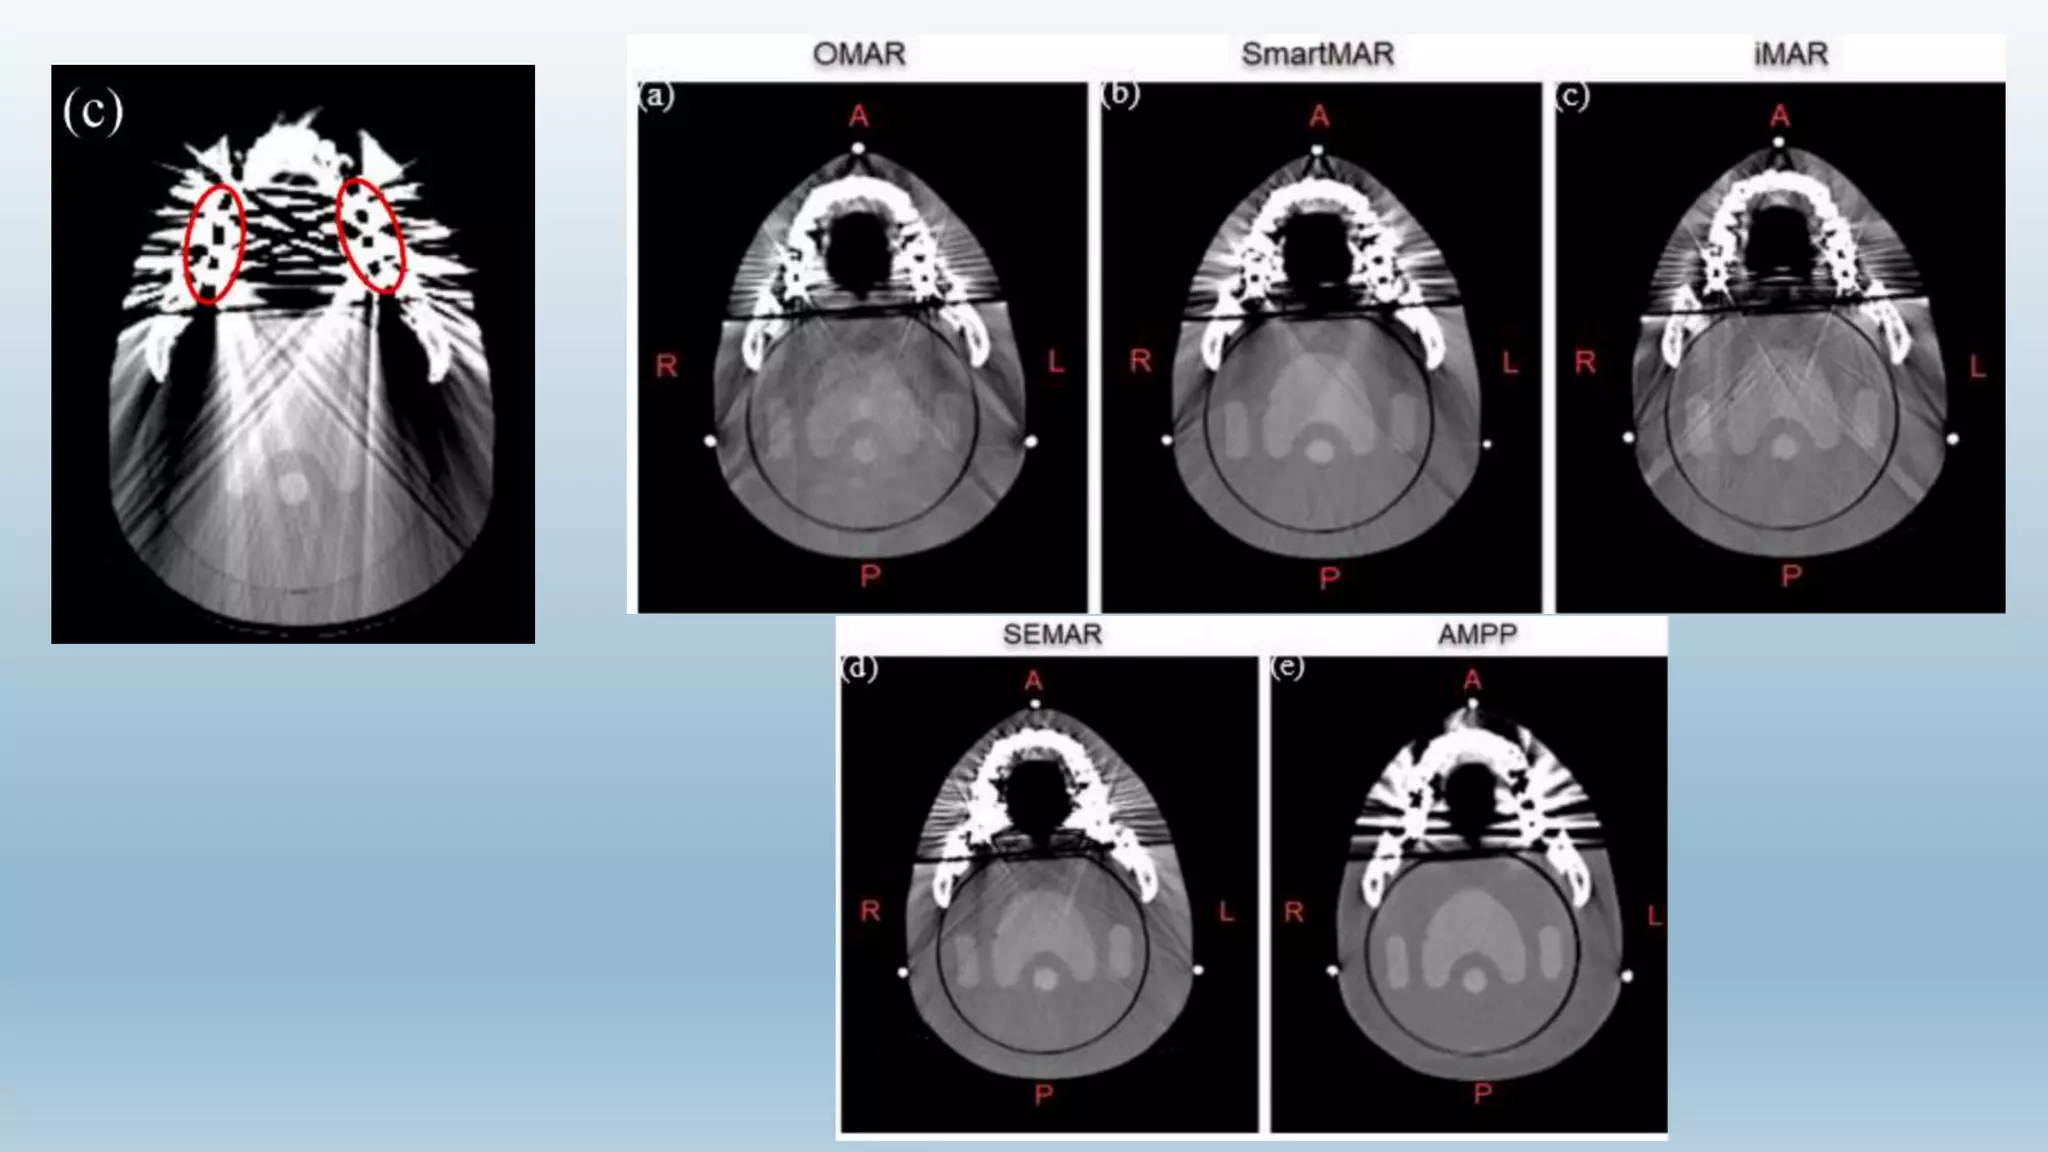

Metal Artifacts

 B. By software correction :-

 Artifact reduction (MAR) algorithms are used to improve CT image quality in patients with metal

ware

 There are a number of commercially-available algorithms (in 2019):

 Iterative MAR (iMAR) - Siemens

 MAR for orthopedic implants (O-MAR) - Philips

 single-energy MAR (SEMAR) - Toshiba/Canon

 SmartMAR – GE

 Beam hardening correction software should also be used when scanning metal objects to minimize

the additional artifacts due to beam hardening.

 The usefulness of metal artifact reduction software is sometimes limited because, although

streaking distant from the metal implants is removed, there still remains a loss of detail around

the metal-tissue interface